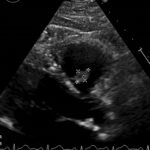

Endovascular coil embolization continues to become a more frequent modality of addressing hemorrhage and bleeding in patients. Migration refers to the coil unraveling or moving from the original embolization site. Migration of a coil is a known complication which can lead to serious consequences based on where the coil migrates. Despite increasing efforts to improve safety and technique, the risk of migration remains. We present a case of an embolization coil that migrated to the right ventricle, which was incidentally found roughly 2 months after undergoing an interventional radiology procedure for gastric variceal bleeding. The patient presented to the emergency department with dyspnea and abdominal pain. Unique images were obtained during his visit and in subsequent follow-up. As use of vascular embolization coils continues to become more commonplace, understanding the risks and complications of these procedures remains an important aspect of providing care for patients once they have left the interventional radiology suite. Coil migration should be a differential to consider in patients who present to the emergency department with signs or symptoms of arrhythmia or pulmonary embolism who have undergone a coil embolization procedure.